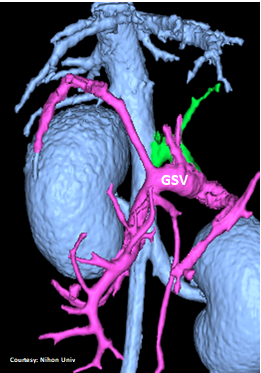

Does the RIGHT GASTRIC VEIN (RGV) contribute blood to the shunt?

WEISSE 2022

slide25